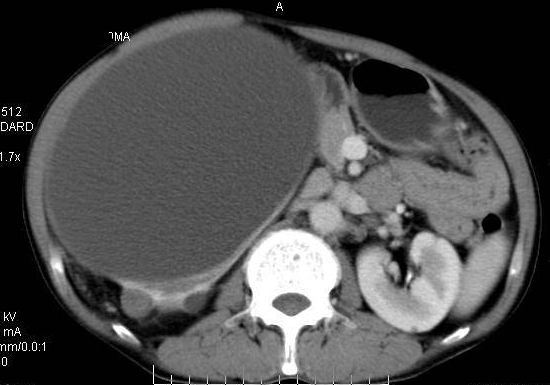

男性 60岁,腹部肿块4年余,肿块逐渐增大,活动性差,无血尿。

动脉期

巨大囊性肿块,囊壁较厚有强化,有团片状钙化,病灶内下方灶内见片絮状高密度影,增强有轻中度强化,考虑囊性肾癌可能性大

右肾上部巨大的囊实性影,实性部分轻度强化。壁有钙化。考虑右肾囊腺癌。右肾盂积水。

定性;病灶囊性为主,前下部含实性成分,及钙化,部分壁厚薄不均。

肾囊实性病变有;1,囊性肾癌2,囊性肾瘤。3,复杂囊肿。4,重复肾伴积水。然2、3壁相对规则。

综上考虑;囊性肾癌》重复肾伴积水。